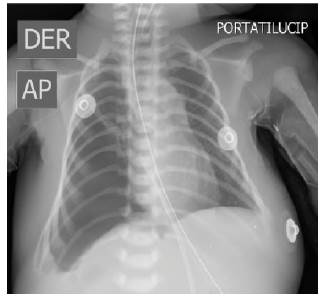

Se realiza radiografía de tórax antero-posterior (Ver figura 1) donde se evidencian asas intestinales en hemitórax derecho que limitan la expansión pulmonar derecha, desplazamiento del mediastino a la izquierda, opacidades en vidrio esmerilado en campo pulmonar izquierdo, matidez hepática en hipocondrio izquierdo y sin evidencia de derrame pleural u otra alteración, confirmando el diagnóstico realizado en la ecografía prenatal, de hernia diafragmática congénita derecha sin herniación hepática e hipoplasia pulmonar derecha severa. Dentro de los diagnósticos diferenciales a considerar se encuentra la malformación adenomatoidea quística pulmonar, aunque en este caso, ante la presentación del cuadro clínico típico y hallazgos en la ecografía prenatal se confirmó el diagnóstico de HDC.

Fuente: autores.

Figura 1 Radiografía de tórax a 12 horas de vida.